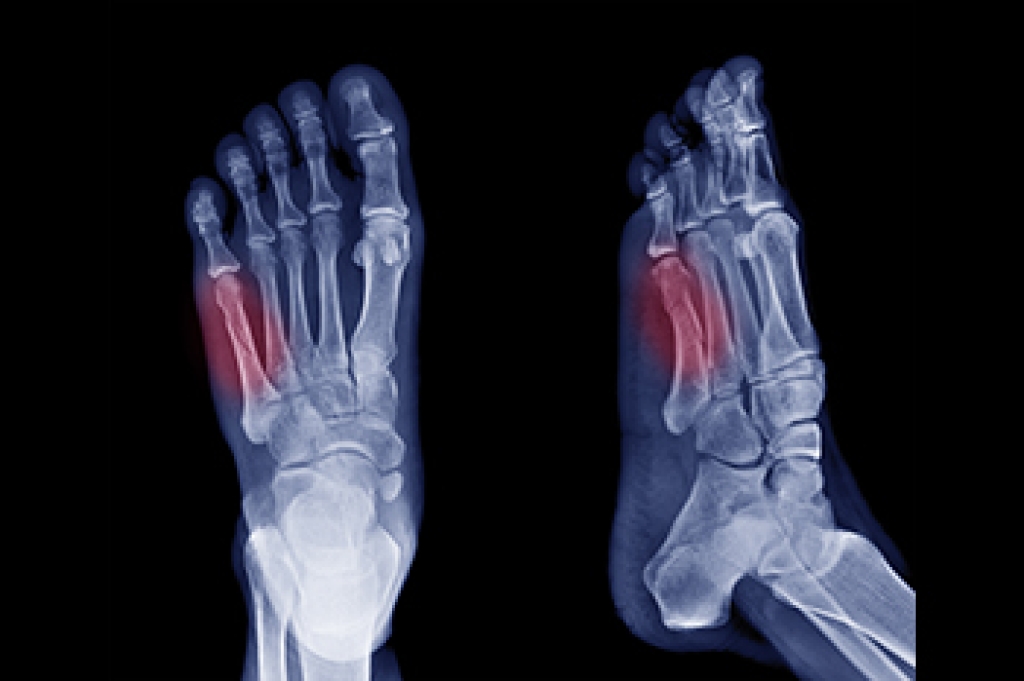

Fractures of the fifth metatarsal occur in various forms, depending on the location and cause of the break. The fifth metatarsal is a long bone located on the outer edge of the foot, connecting the midfoot to the base of the pinky toe. It plays an important role in maintaining balance, supporting weight, and enabling movement during activities such as walking, running, and jumping. Avulsion fractures, the most frequent type, happen when a tendon pulls a small piece of bone off the base of the fifth metatarsal. Dancer’s fractures, caused by twisting injuries, involve a diagonal break along the bone’s shaft. Stress fractures, resulting from repetitive activities like running, develop gradually and often affect the shaft or neck. Head and neck fractures of the 5th metatarsal typically occur from direct trauma to the bone. A podiatrist can use imaging tests to determine the type of fracture you have sustained. For guidance with a fractured foot bone, it is suggested that you schedule an appointment with a podiatrist for a diagnosis and treatment options.

A broken foot is caused by one of the bones in the foot typically breaking when bended, crushed, or stretched beyond its natural capabilities. Usually the location of the fracture indicates how the break occurred, whether it was through an object, fall, or any other type of injury.

Treatment for broken bones varies depending on the cause, severity and location. Some will require the use of splints, casts or crutches while others could even involve surgery to repair the broken bones. Personal care includes the use of ice and keeping the foot stabilized and elevated.